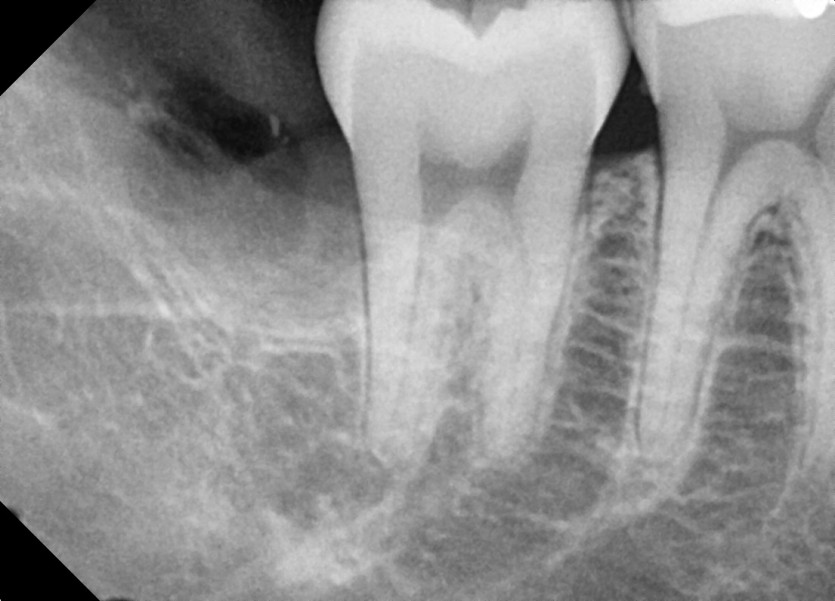

#18,28,38,48 사랑니 발치 (#19과잉치 포함)

구강 외과 전문의가 당일 발치했습니다.